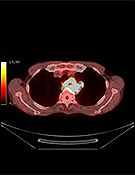

当院では、PET検査と同時にCT検査が行える最新鋭機器『PET-CT』を導入しました。これにより、検査時間の短縮はもちろんのこと、PETによる細胞の機能診断画像とCTによる形態診断画像を重ね合わせることで、診断精度が大幅にアップします。

| <PET/CT Fusion画像> | <PET/CT Fusion画像> | <PET画像> | <MIP画像> |